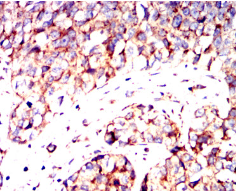

IRF3 Mouse Monoclonal antibody[5G3E2]

This gene encodes a member of the interferon regulatory transcription factor (IRF) family. The encoded protein is found in an inactive cytoplasmic form that upon serine/threonine phosphorylation forms a complex with CREBBP. This complex translocates to the nucleus and activates the transcription of interferons alpha and beta, as well as other interferon-induced genes. The protein plays an important role in the innate immune response against DNA and RNA viruses. Mutations in this gene are associated with Encephalopathy, acute, infection-induced, herpes-specific, 7.

IHC    1/200 - 1/1000